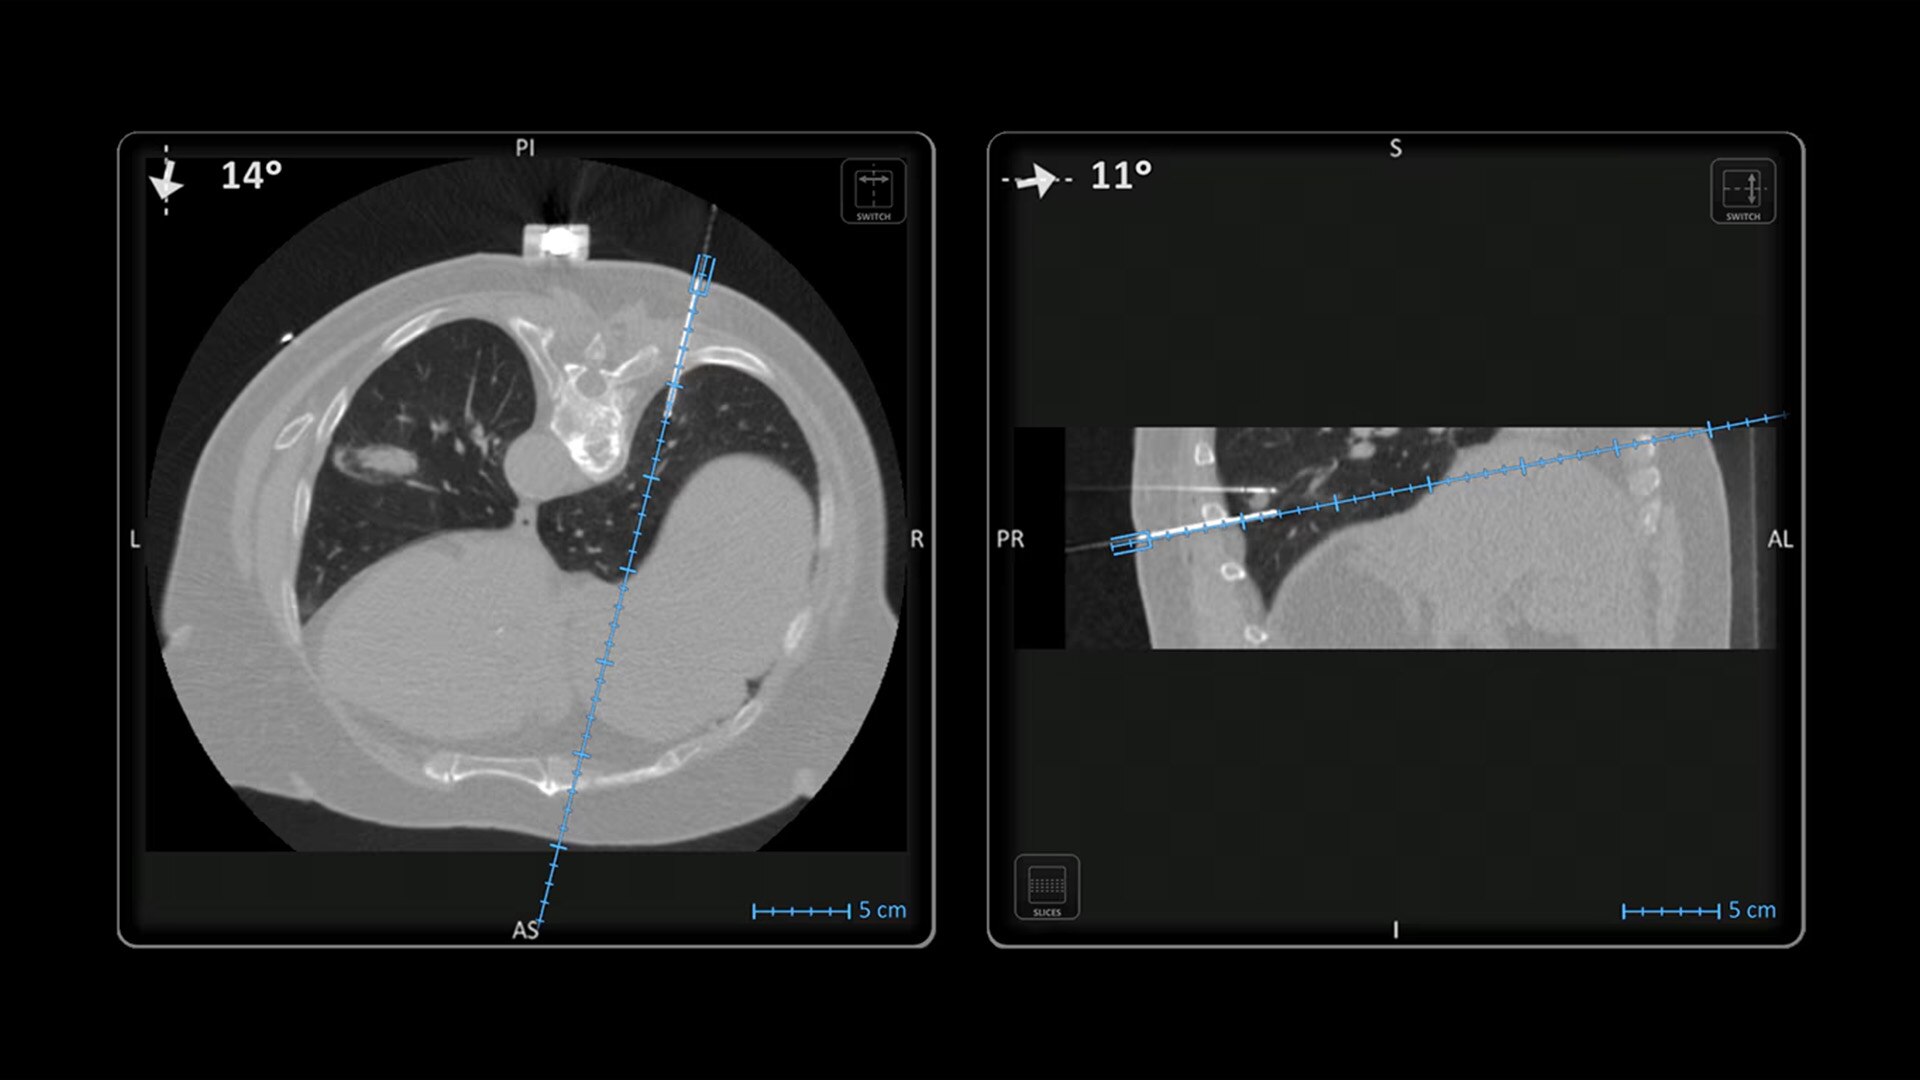

In interventional radiology, the success of the percutaneous procedure depends on correct needle positioning. The Imactis system helps the radiologist place one or more needles with great accuracy, in less time and with fewer control scans.

With real-time image reconstruction, live interactive navigation and no limit in angulation, the optimal clinical choices are clear.

Live 3D needle tracking, precise reproduction of your planned trajectory and continuous needle depth measurement help ensure optimal needle placement.